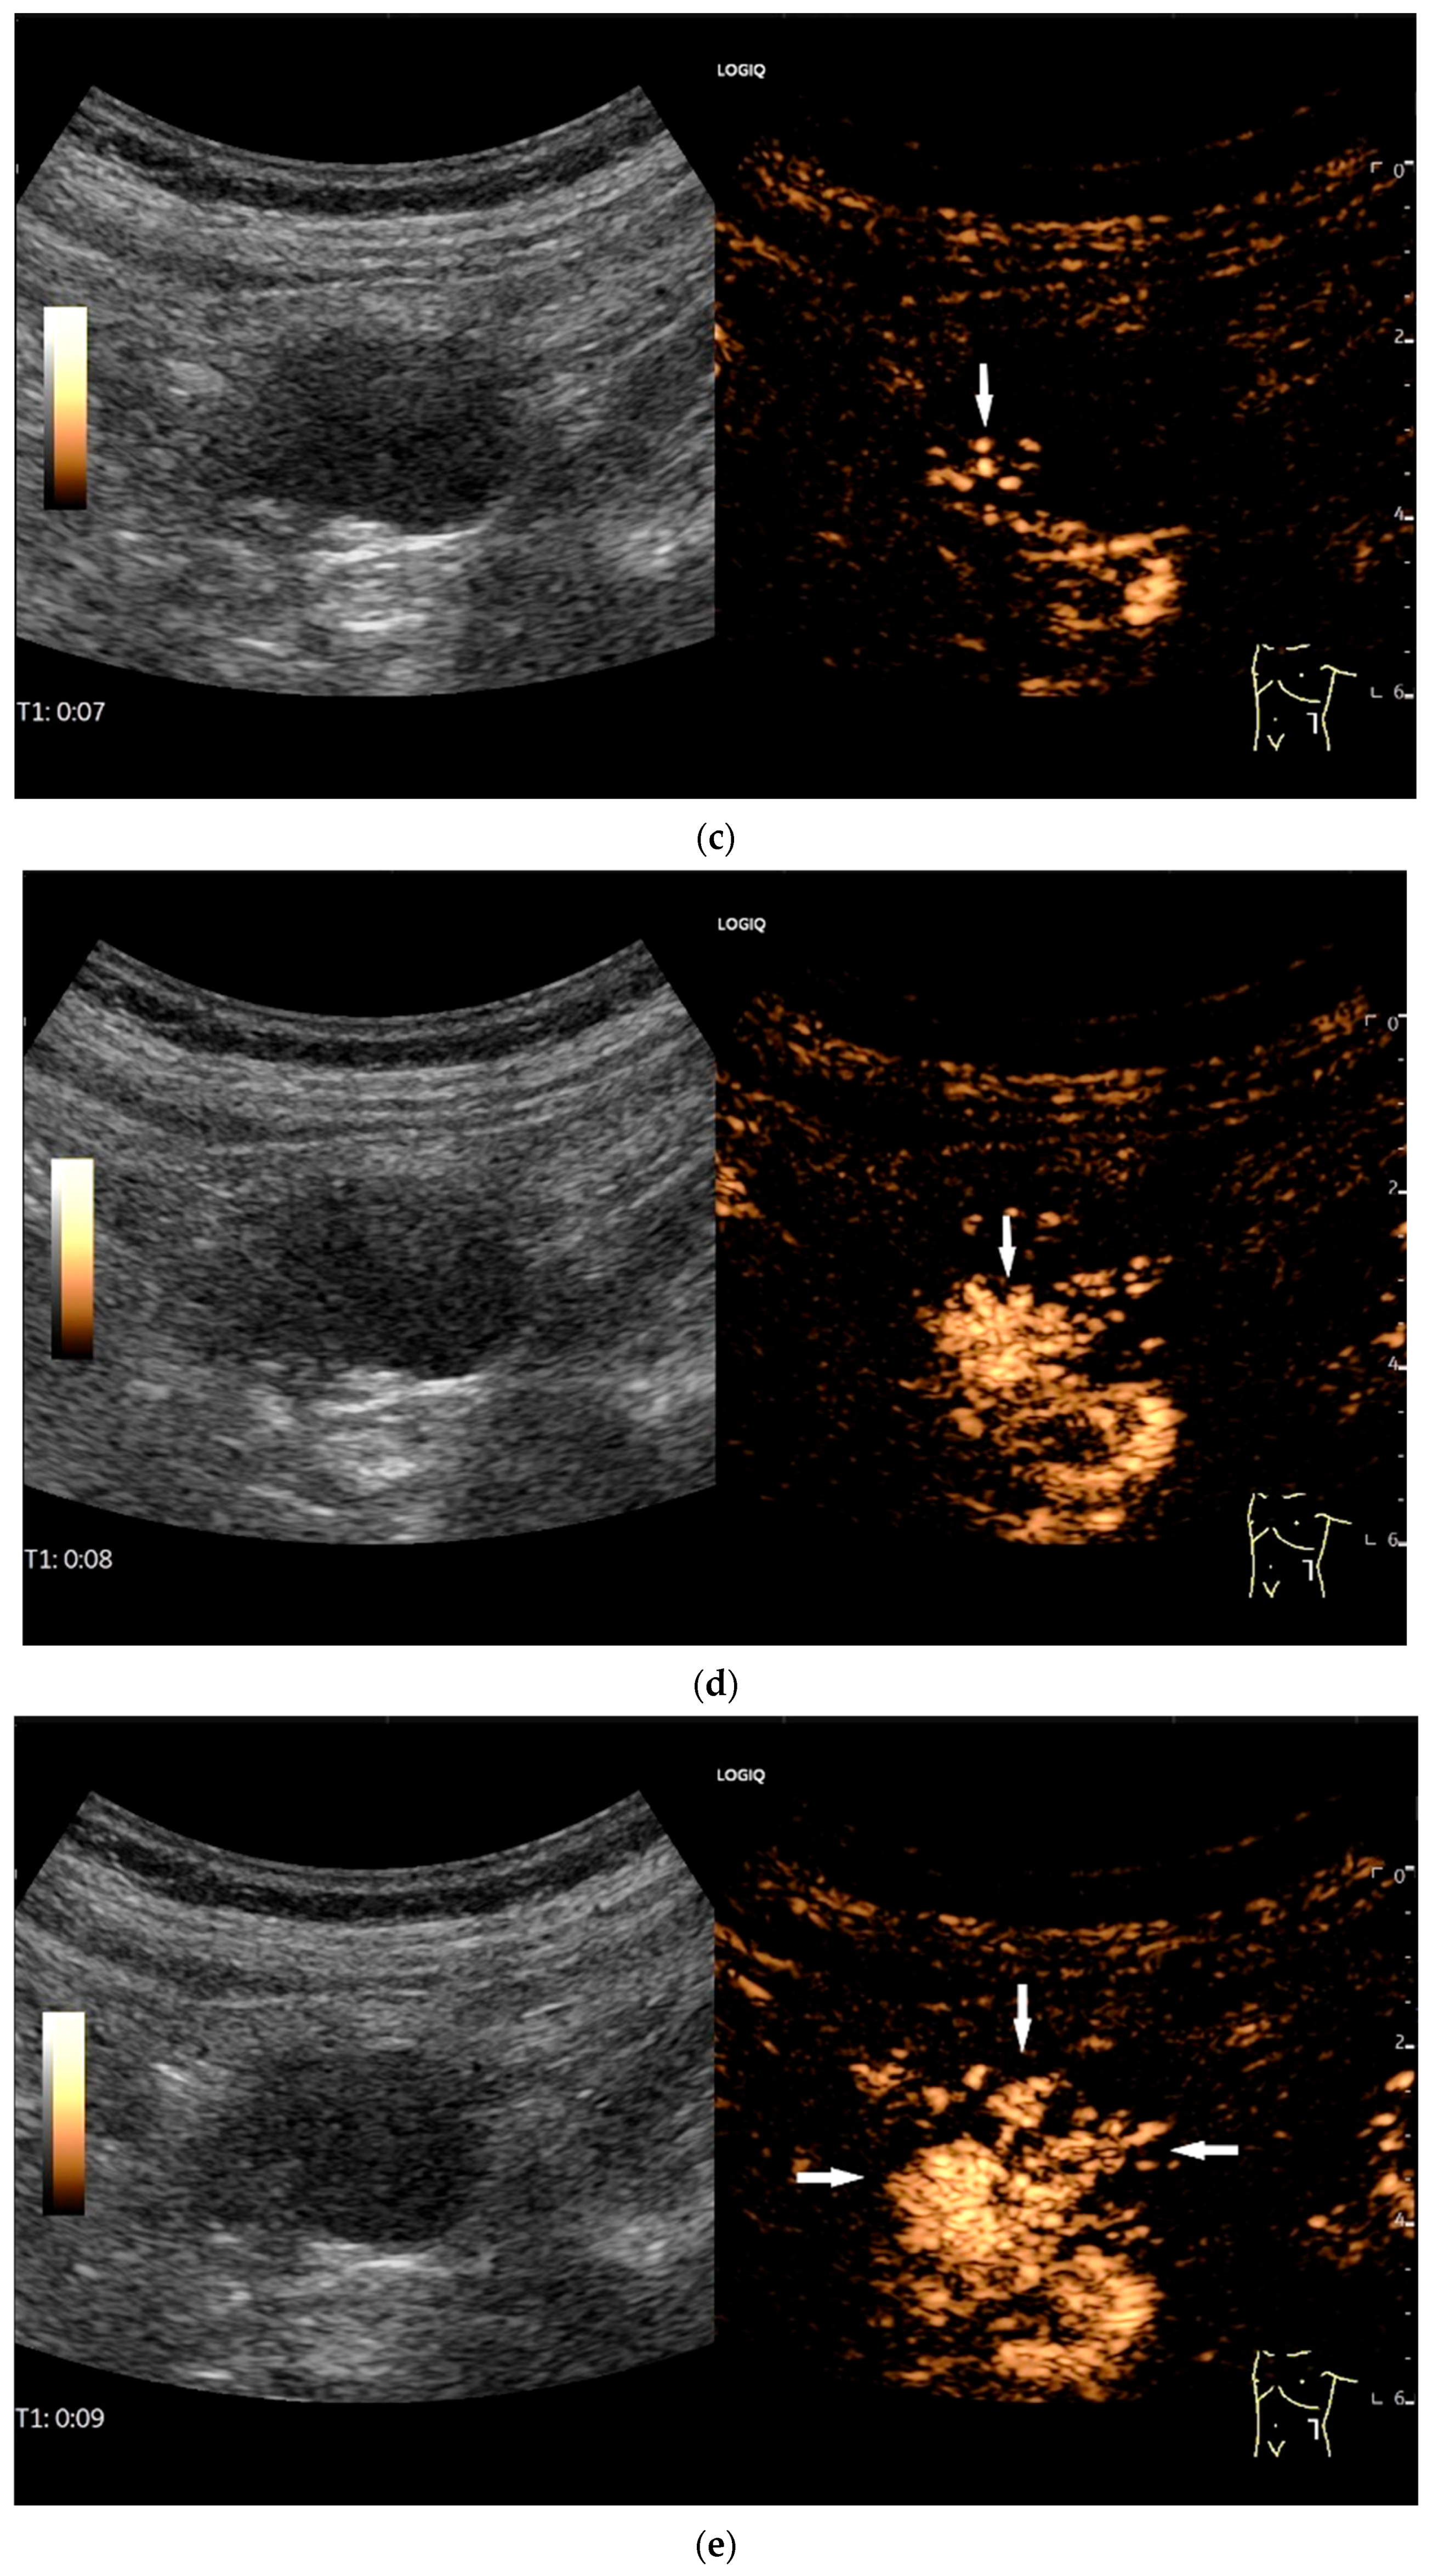

- Cui, N.Y.; Gong, X.T.; Tian, Y.T.; Wang, Y.; Zhang, R.; Liu, M.J.; Han, J.; Wang, B.; Yang, D. Contrast-enhanced ultrasound imaging for intestinal lymphoma. World J. Gastroenterol. 2021, 27, 5438–5447. [Google Scholar] [CrossRef]

| Lymphoma | Very pronounced wall thickening with marked hypoechogenicity. Large regional and distant lymph nodes. Look for splenic infiltration. Tumor vessels on CDI and hyperenhancement on CEUS. Heterogeneous hyperechogenicity of the mesentery with walling of the mesenteric vessels. Multiple localizations are possible. |